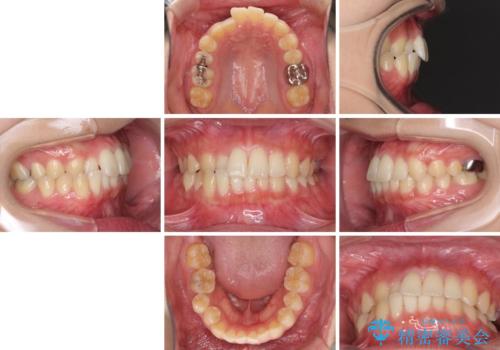

海外勤務中のインビザラインによる矯正治療

- 患者様

- 20代女性

- 矯正装置

- インビザライン

- 治療期間

- 1年6ヶ月

- 治療回数

- 10-30回